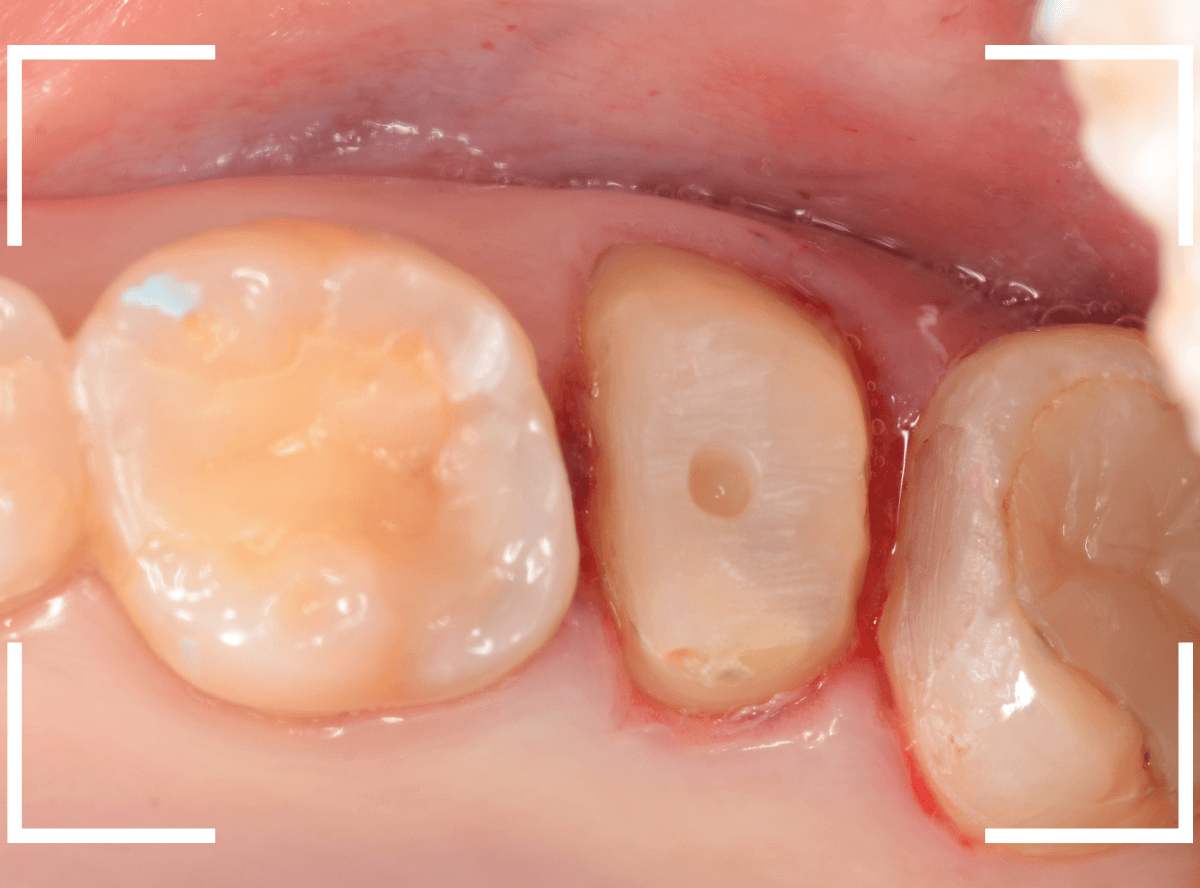

さし歯の土台の補修と、おやしらずの虫歯の処置をしたところです。

この状態で型をとります。

模型上で精密に製作します。